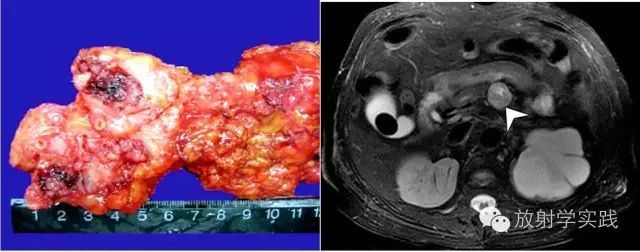

ACCP从肿瘤分化水平高至低,肿块可表现为等、等低、等密度影,坏死是其特征表现,表现为裂隙状、漩涡中,即使肿块很小也会出现坏死[16],由于ACCP间质内血窦丰富,也易发生出血(图6)。PASC含有>30%鳞状上皮成分,该成分易于囊变坏死,影像上也表现为囊实混合肿块(图7)。

图8 嗜酸性胰腺导管内乳头状黏液瘤(IOPN)。a)大体病理标本,显示分支胰管内实性肿块(箭);b)横轴面T2WI示胰体部圆形肿块呈稍高信号(箭),中心可见点状高信号。